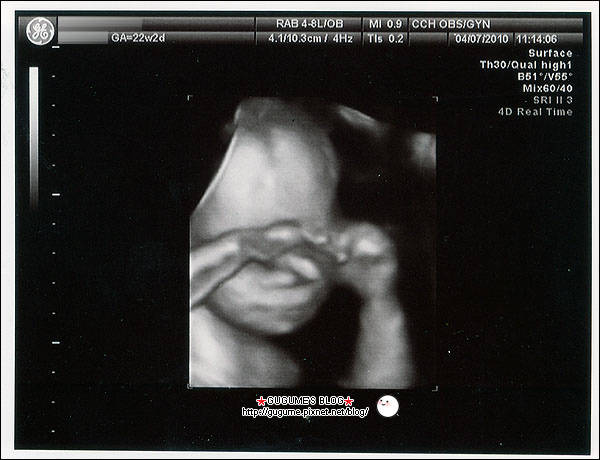

記得產檢時你一直都是很害羞的狀態

常都用小手遮臉不讓阿母看